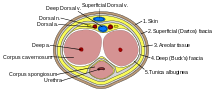

Cross-section of the human penis

Penile trauma can result from a blunt or penetrating injury, the latter being rarely investigated by imaging methods, almost always requiring immediate surgical exploration. In the erect penis, trauma results from stretching and narrowing of the tunica albuginea, which can undergo segmental rupture of one or both of the corpora cavernosa, constituting a penile fracture.[2]